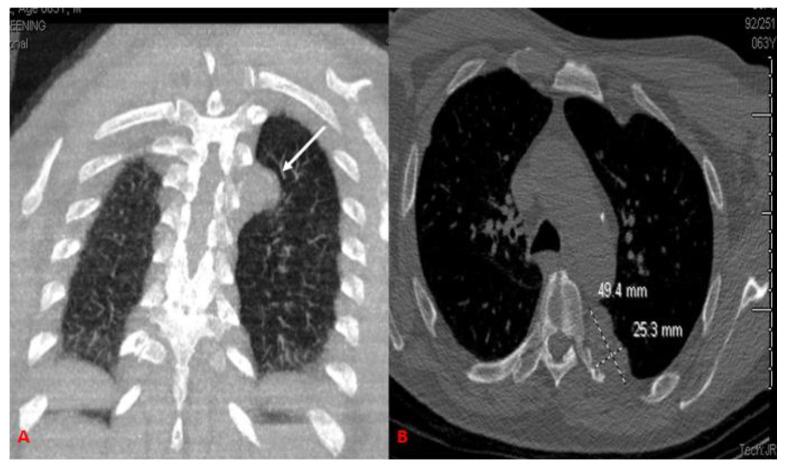

Leiomyomas are a common type of benign soft tissue tumor arising from smooth muscle, most often occurring within females' genitourinary and gastrointestinal tract. However, primary leiomyomas of the chest wall residing in the extra-pleural space are an extremely rare subset of leiomyomatous lesion presentation. We present a case of a fifty-two-year-old male who initially presented complaining of dyspnea worsening with exertion. Computed tomography imaging was performed showing an extra-pleural mass residing under the left sixth rib. Subsequent core needle biopsy and immunohistochemical staining were performed, and the definitive diagnosis of primary leiomyoma of the posterior mediastinal chest wall. Although extremely rare, this neoplastic condition should be included in your differential diagnosis when diagnostic imaging reveals a benign mass residing in the extra-pleural space, and subsequent biopsy specimens consist of smooth muscle fibers.

平滑肌瘤是一种常见的良性软组织肿瘤,来源于平滑肌,最常发生于女性的泌尿生殖系统和胃肠道。然而,位于胸膜外的胸壁原发性平滑肌瘤是平滑肌瘤病变的一个极其罕见的亚型。我们报告了一例 52 岁男性患者,最初表现为进行性加重的呼吸困难。行计算机断层扫描成像显示位于左第六肋骨下的胸膜外肿块。随后进行了芯针活检和免疫组织化学染色,明确诊断为胸后壁后纵隔原发性平滑肌瘤。尽管极其罕见,但当诊断性影像学显示位于胸膜外的良性肿块且活检标本包含平滑肌纤维时,应将这种肿瘤性病变纳入鉴别诊断。